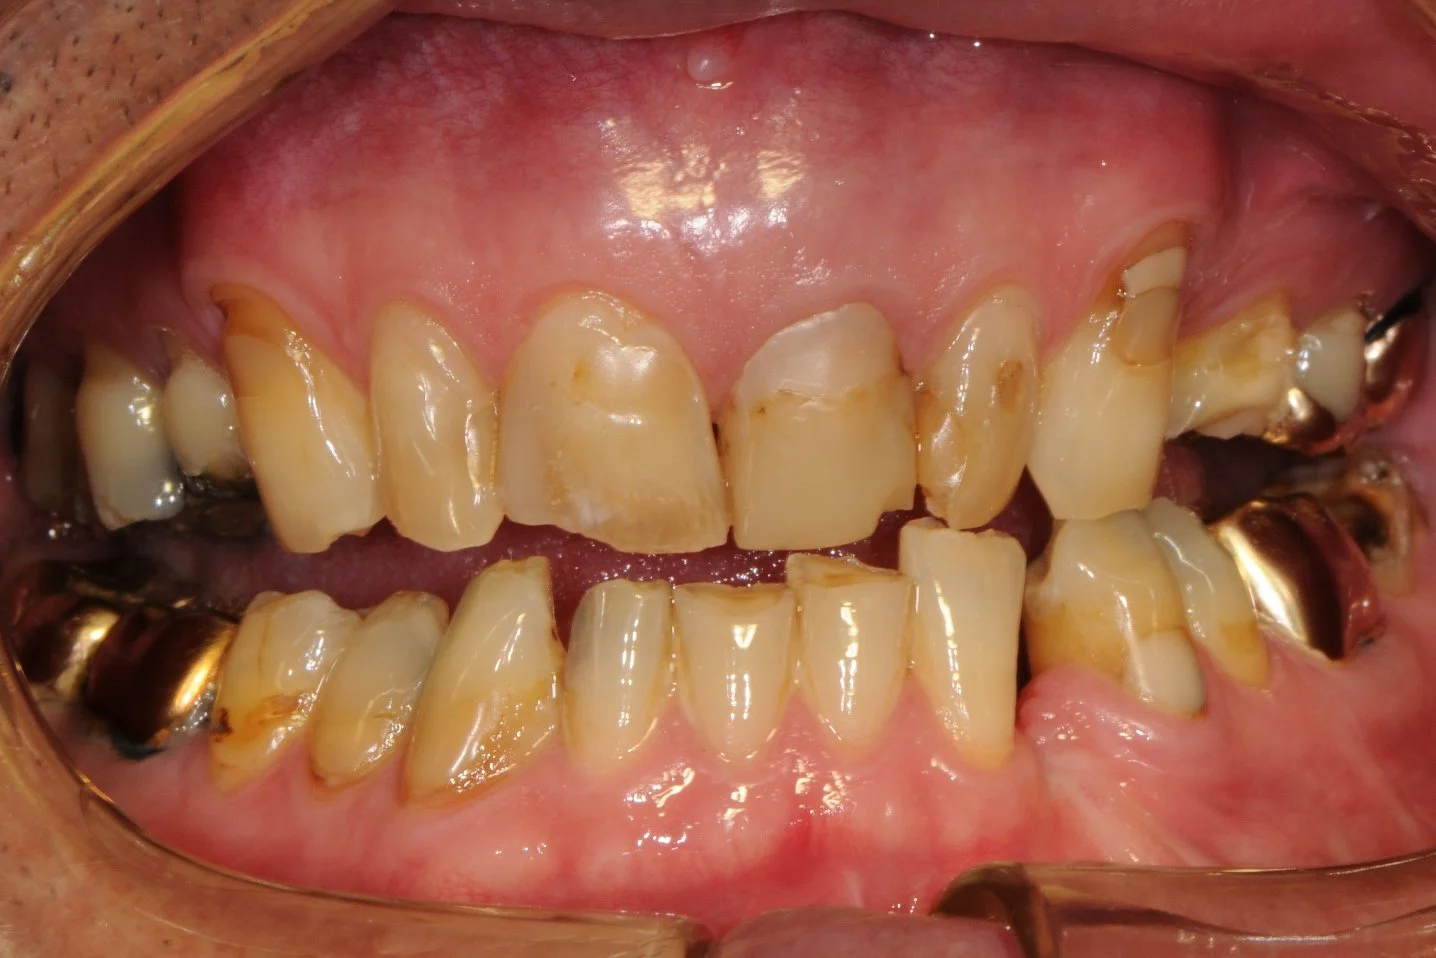

This 50 year old gentleman suffered severe dental wear, and heavily filled and stained teeth.

-

He endured a fractured lower jaw from a car accident resulting in the loss of the lower left canine with a residual space and a metal splint to fixate the broken jaw as is illustrated